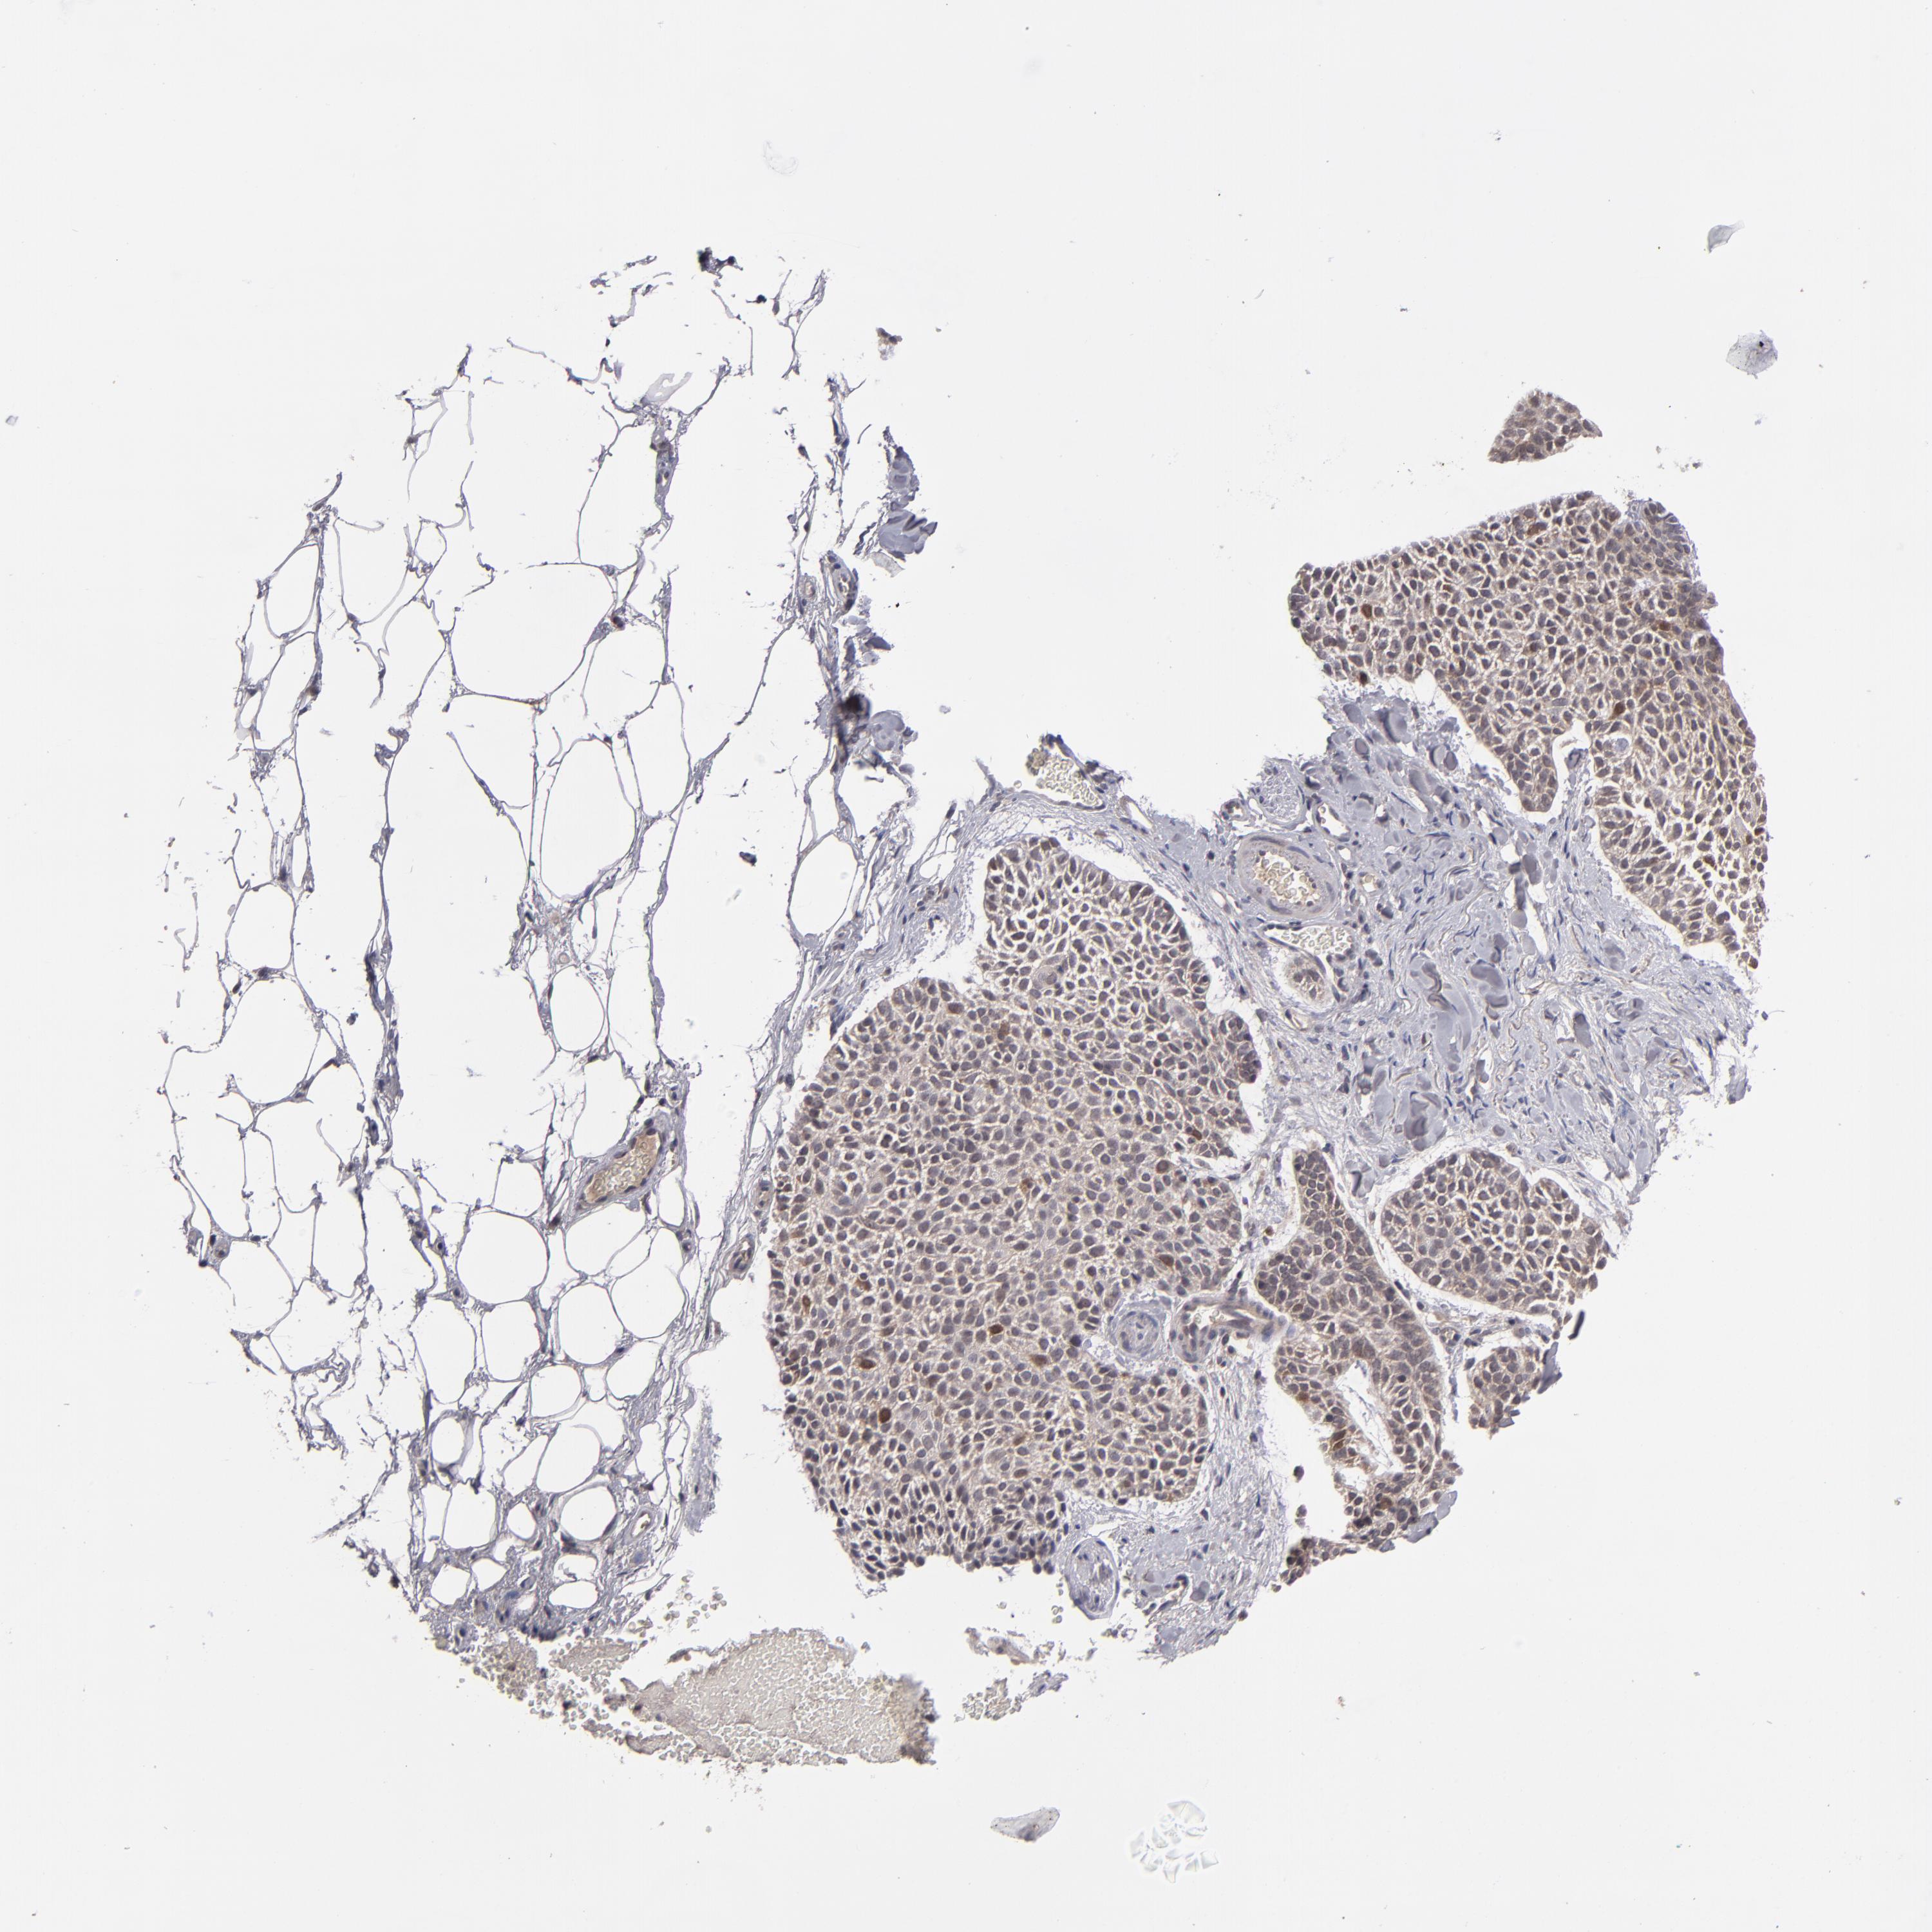

SKIN CANCER - Protein expressioni

A mouse-over function shows sample information and annotation data. Click on an image to view it in a full screen mode. Samples can be filtered based on level of antibody staining by selecting one or several of the following categories: high, medium, low and not detected. The assay and annotation is described here.

Antibody stainingi

Antibody staining in the annotated cell types in the current human tissue is reported as not detected, low, medium, or high, based on conventional immunohistochemistry profiling in selected tissues. This score is based on the combination of the staining intensity and fraction of stained cells.

Each image is clickable and will lead to virtual microscopy that enables deeper exploration of all samples and also displays staining intensity scores, fraction scores and subcellular localization as well as patient and tissue information for each sample.

Antibody HPA074922

Antibody CAB002784

Basal cell carcinoma

Squamous cell carcinoma, NOS